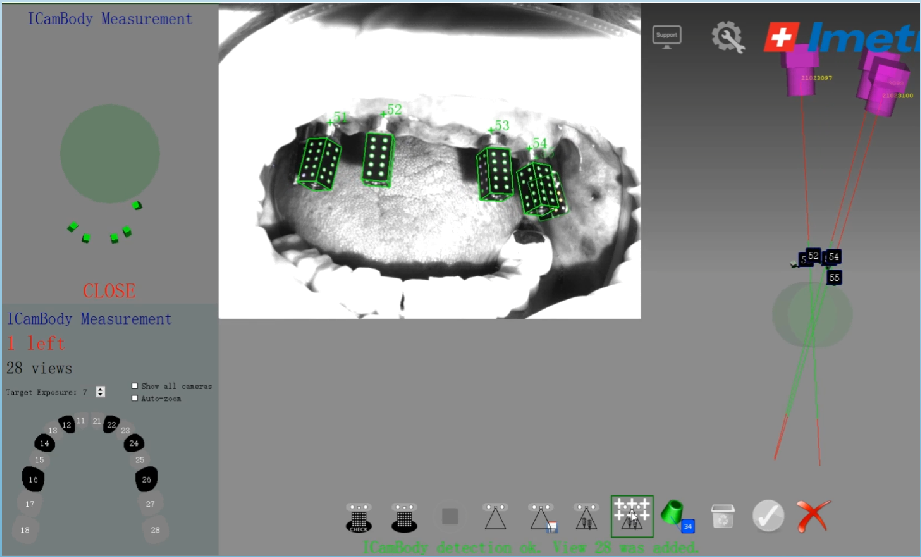

真实案例

TRUE CASE

数字化

数字化义齿智能制造工厂

数字CAD设计工程师研发团队

个性化精准医学3D打印技术